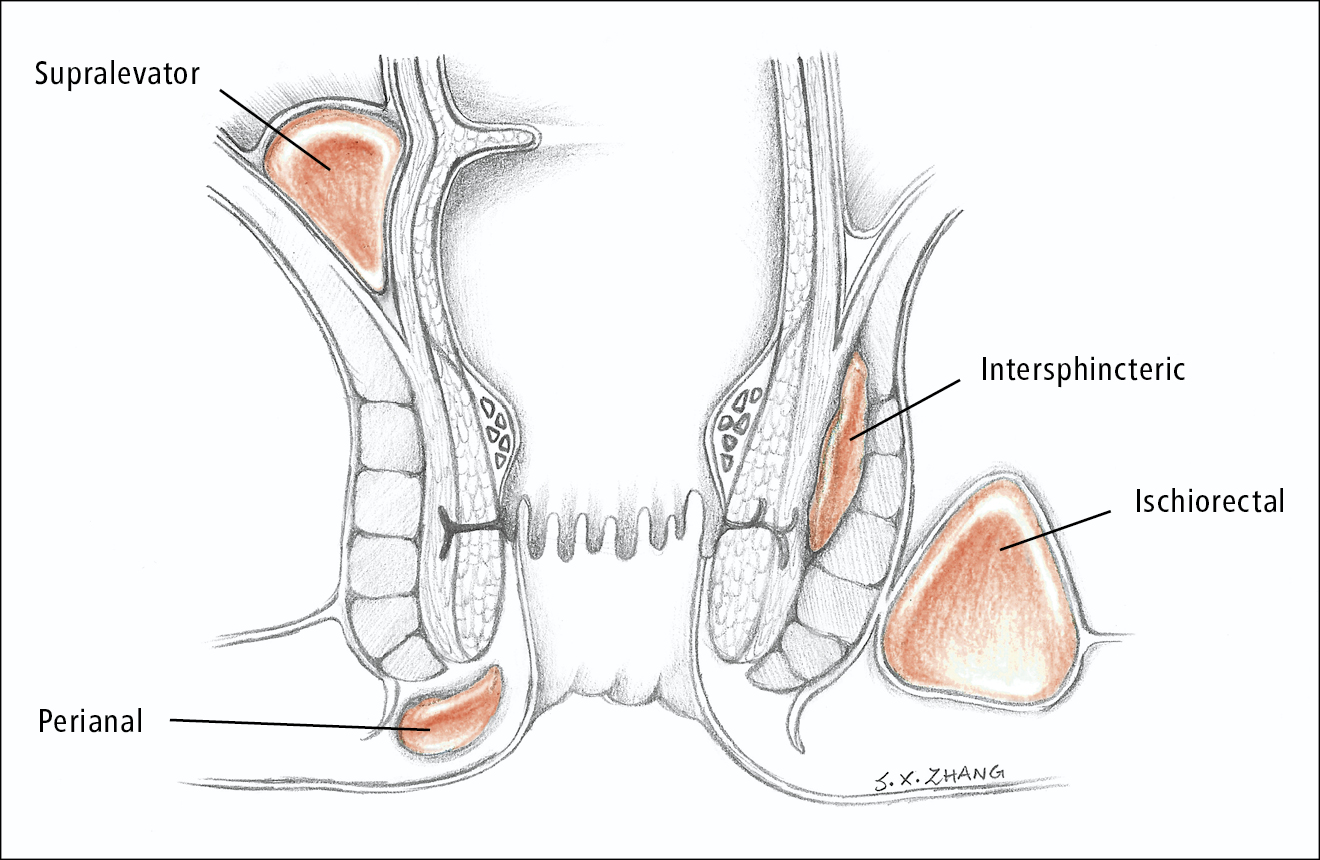

An anorectal abscess is a painful collection of pus near ...

If you experience recurring pus discharge or pain around the anal ...

If you have been dealing with pain, swelling, or pus near the anus that keeps coming back ...